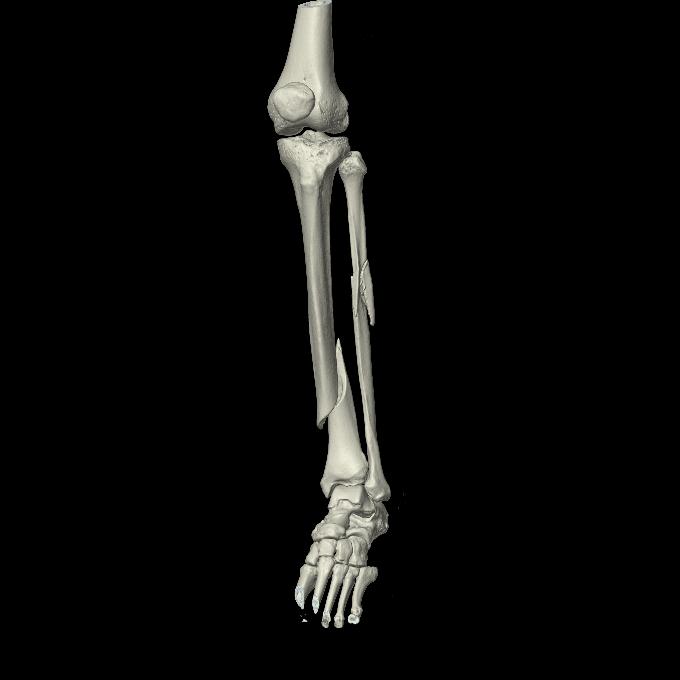

102803 1/12(キウスなし) 1/27 左下腿 4R 30歳女性 左脛骨軸内釘